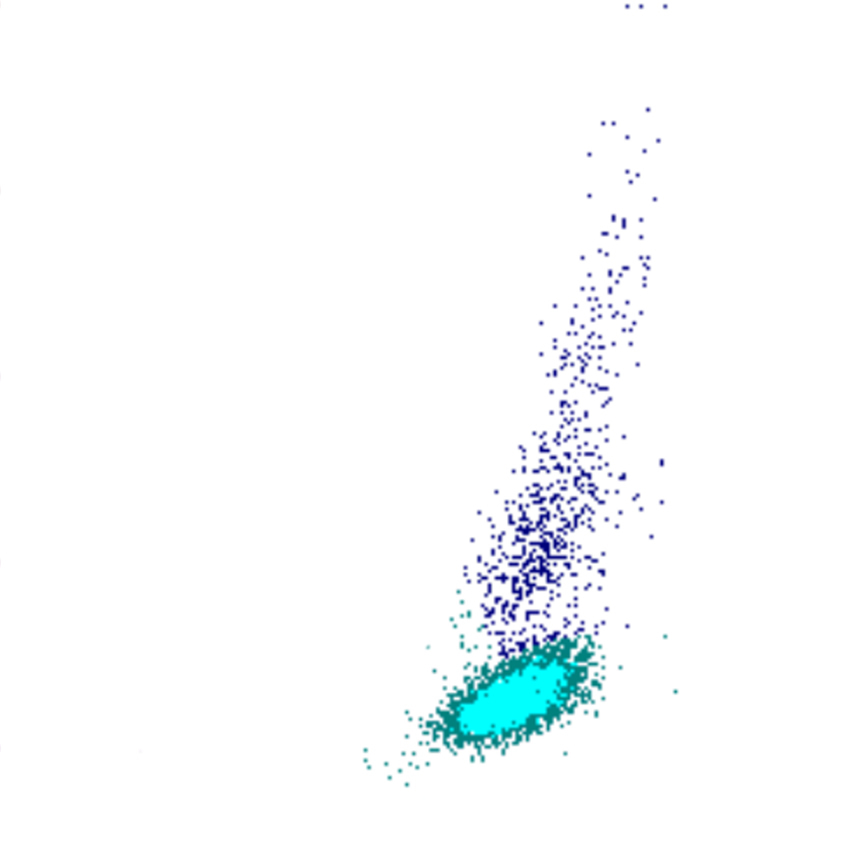

Forward Scatter

Le FSC est une mesure de la taille cellulaire : des valeurs élevées de FSC indiquent des cellules plus grandes, tandis que des valeurs plus faibles correspondent à des cellules plus petites. Les plaquettes présentent le FSC le plus bas, tandis que les monocytes, les lymphocytes plasmocytoïdes et certains blastes figurent parmi les cellules les plus volumineuses.

FSC scatter

FSC faible

FSC élevé